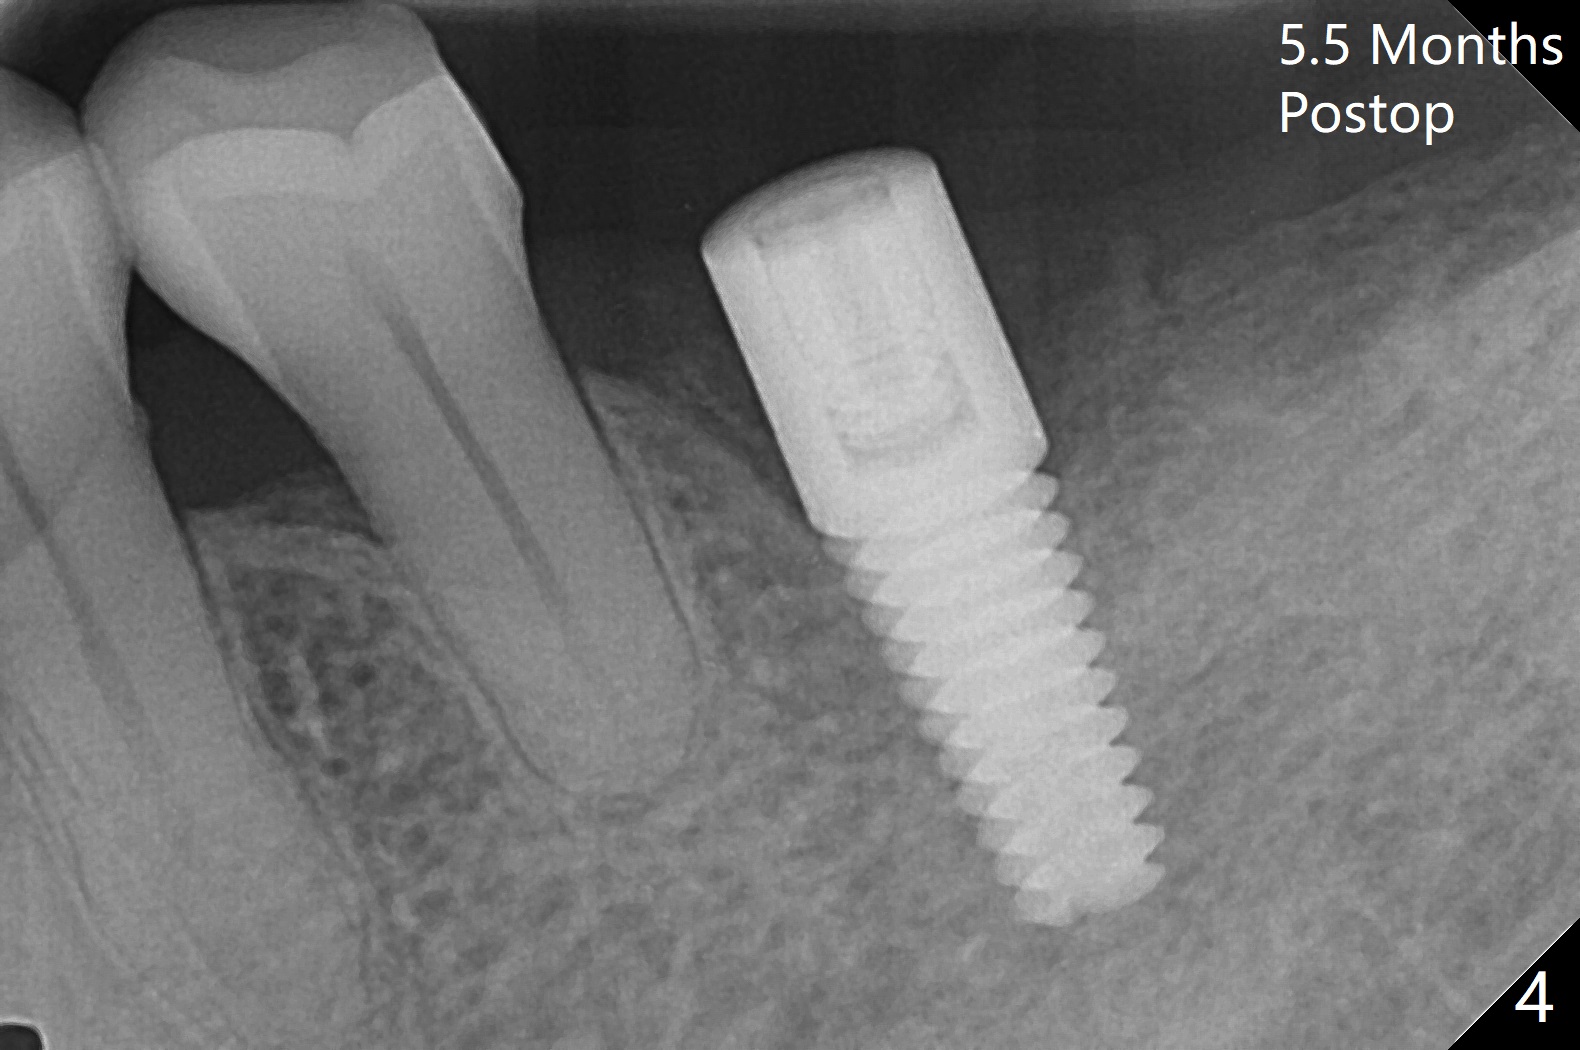

Following light use of 4 mm tissue punch, a buccal incision is made and raised. After 4x8.5 mm drill with 10.5 mm offset at #19, 4.5 mm cortical drill is used for 2/3 length to take care of the thick dense lingual plate (overprep). The remaining apical 3 mm osteotomy is underdrill (3.5 mm). After try-in of a 4.5x14 mm tissue-level dummy implant, a same-sized definitive one obtains 35 Ncm torque (Fig.1). Following 3-4 more turns, the torque reaches 45 Ncm (Fig.2) with the distal thread covered (<) and autogenous bone graft placed in the distal defect (*). A 4x3 mm unipost is placed to keep periodontal dressing in place. Clinically the implant is placed within bone boundary buccolingually. The new implant seems necessary considering short (Fig.2 S) and probably resorbed (Fig.1 R) roots of the premolars. In fact the short abutment keeps the mesiolingual portion of periodontal dressing for 2 weeks; since local hygiene is suboptimal, the healing screw is placed after abutment and dressing removal (Fig.3).